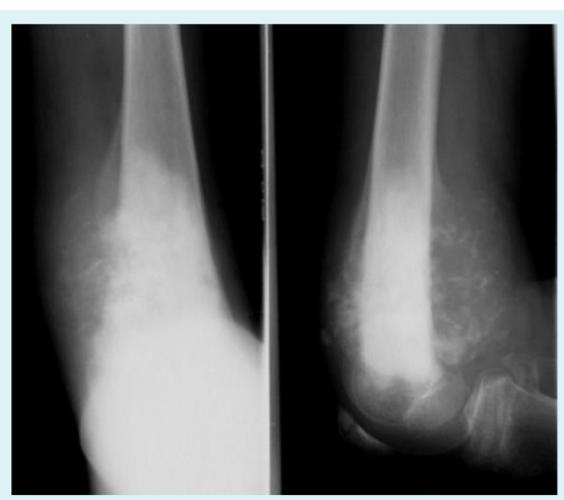

What are the characteristic x-ray findings in rickets?

- Widening of the epiphyseal plate

- Cupping of the metaphysis

- Irregular metaphyseal ends

- Widened physis

A 5-year-old boy was brought to the clinic because of a progressively increasing deformity in his left leg for 6 months.

What are the abnormal x-ray findings?

- Widening of epiphyseal plate

- Cupping of metaphysis

How will you treat the underlying cause?

- Vitamin D supplementation